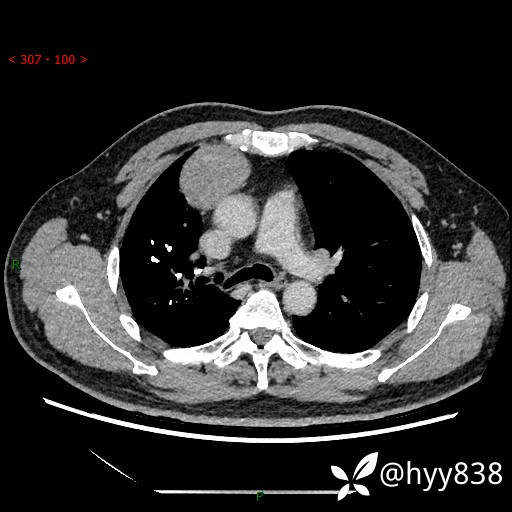

胸部CT平扫

动脉期+静脉期

各期CT值